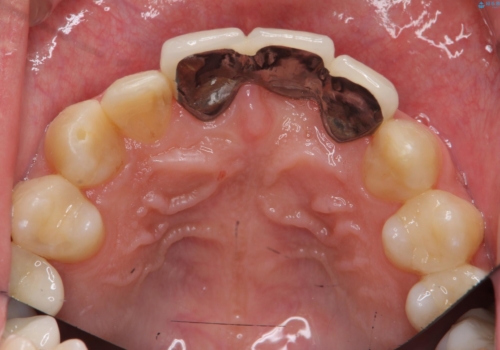

- 以前、前歯にボールが当たりダメになってしまって抜歯したが、そこにとりあえず接着剤で歯をつけて生活していたとのこと。

両側の歯の接着剤の周りが虫歯になってしまっていました。

両側の歯の虫歯をしっかりとってブリッジにすることにしました。

欠損部に長年薄いプラスチックの仮の歯を留めていたため、下の歯が食い込みさらにブリッジのポンティックの隙間がない状態でした。そのため、かみ合わせが深く、下の歯との隙間がかなりなかった為、事前の矯正治療をお勧めしましたが、希望されず特に行わずそのまま虫歯治療を行うことになりました。